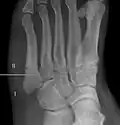

Jones fracture as seen on Xray

Diagnostic X-rays include anteroposterior, oblique, and lateral views and should be made with the foot in full flexion.

Zones I and III have been associated with relatively guaranteed union and this union has taken place with only limited restriction of activity combined with early immobilization. On the other hand, zone II has been associated with either delayed or non-union and, consequently, it has been generally agreed that fractures in this area should be considered for some form of internal immobilization, such as internal screw fixation.

These zones can be identified anatomically and on x-ray adding to the clinical usefulness of this classification.[21] Surgical intervention is not, by itself, a guarantee of cure and has its own complication rate. Other reviews of the literature have concluded that conservative, non-operative, treatment is an acceptable option for the non-athlete.[22]